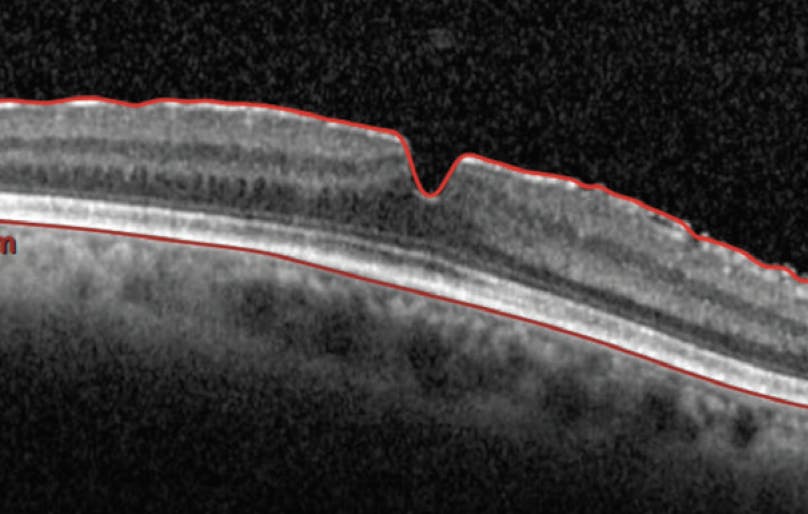

Vitreous Opacities With Progressive ERM—and 20/20 VA

A middle-aged phakic man presented to my clinic. He was a professional photographer who reported symptomatic vitreous opacities (VOs). Clinical examination including OCT (Figure 1) showed that he had 20/20 VA, no signs of cataract, bilateral posterior vitreous detachment (PVD), and average floaters. I advised that he wait 6 months before considering surgery.

The patient returned in 5 months reporting that his VOs had worsened and that neither eye was noticeably worse than the other. OCT imaging of the patient’s right eye (OD) showed the presence of an epiretinal membrane (ERM) and the loss of foveal contour (Figure 2); the left eye (OS) was unchanged. The patient continued to have 20/20 VA.

Pars plana vitrectomy was performed OD. Per my usual methodology, I aimed to remove only the tissue easily reached (ie, what was detached and available). After removal of vitreous, I used forceps to initiate an ERM peel.

The patient remained 20/20 on postoperative day 1. By postoperative week 5, foveal contouring had begun to return OD (Figure 3). Like most patients who have had successful surgery for the removal of symptomatic VOs, he is eager to undergo surgery in the contralateral eye.